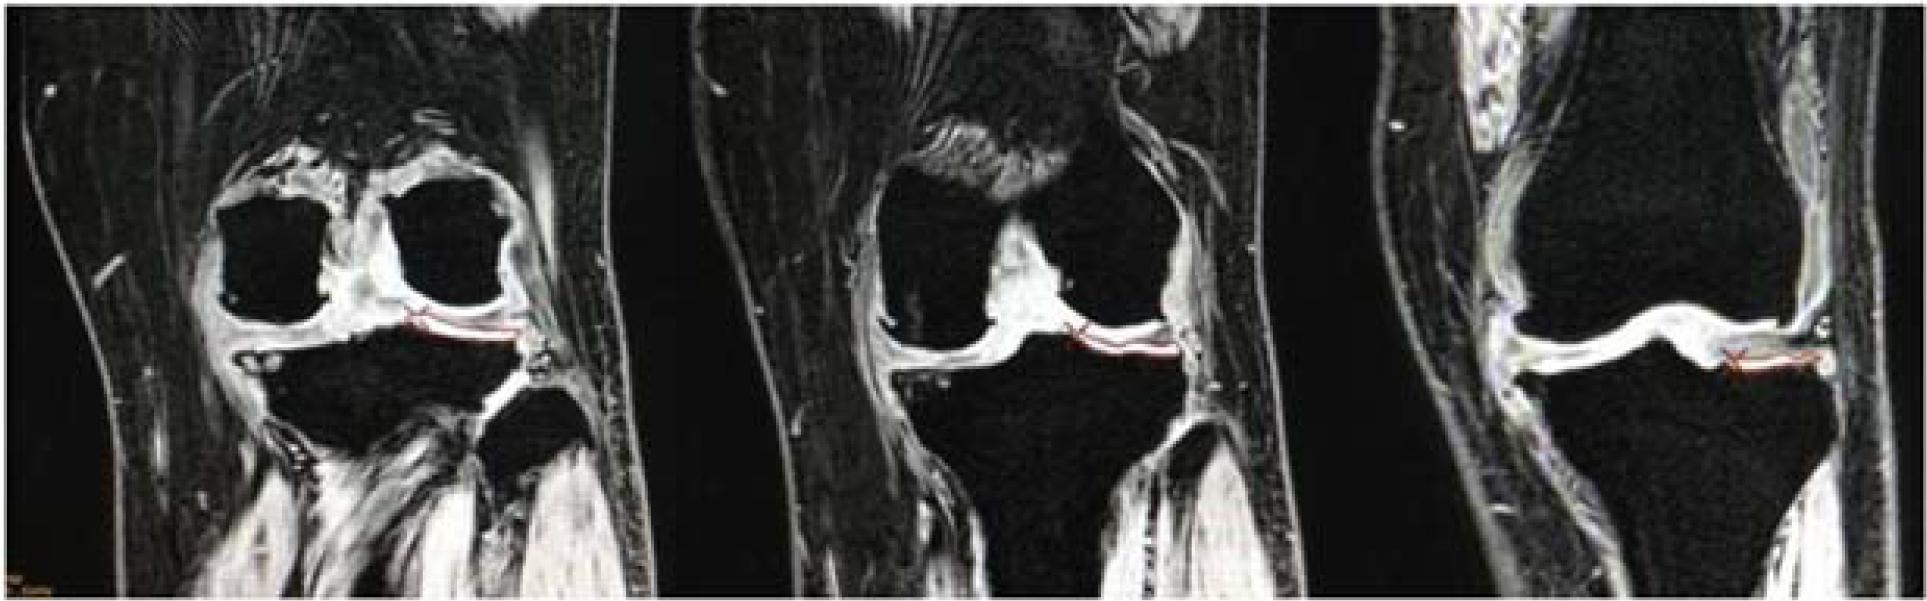

Figure 1

Figure 2

Figure 3

Figure 4